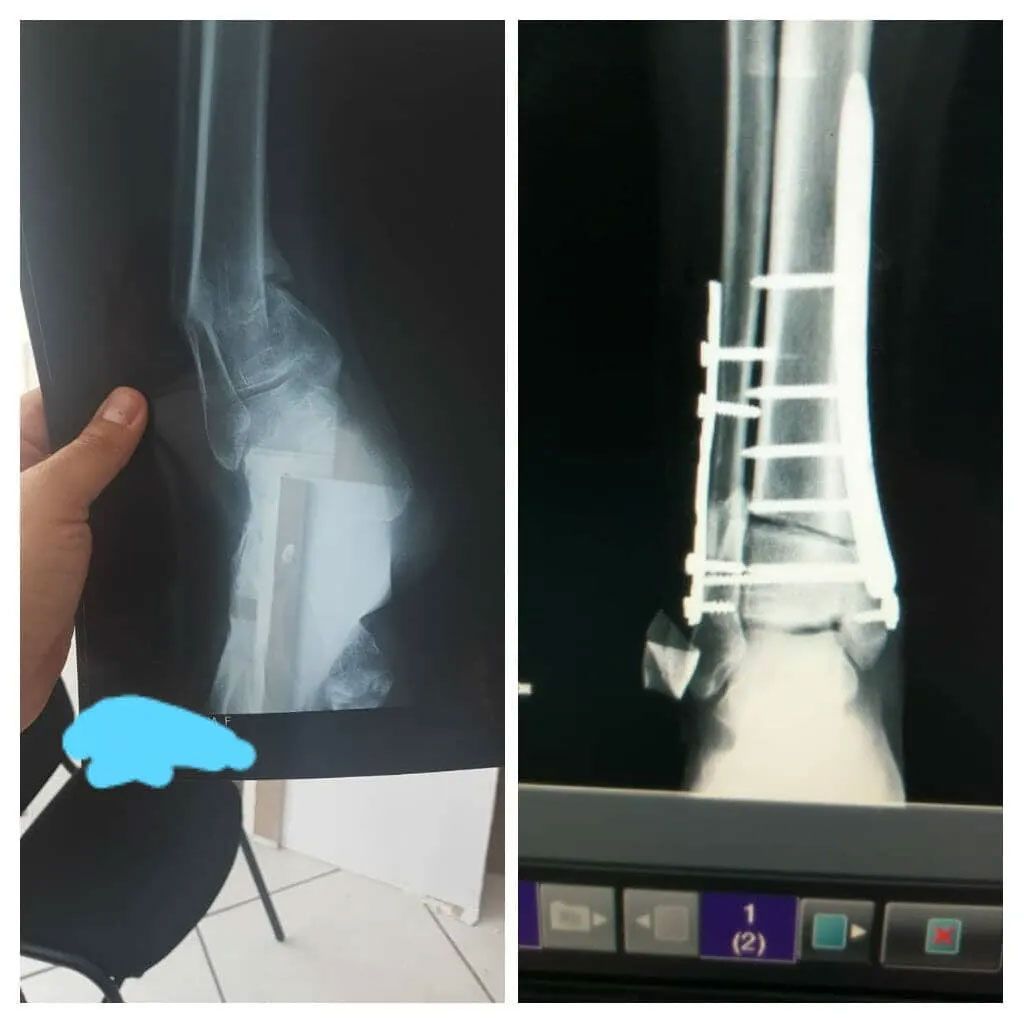

- Cirugía de fracturas

DR. DIEGO CORRAL ACOSTA -Masculino de 25 años. Accidente en motocicleta con contusión en antebrazo. Presenta una fractura de radio con luxación del cubito conocida con el nombre de Fractura de Galeazzi. Se le realizó la reducción y fijación de la fractura solucionando la luxación del cubito al mismo tiempo. El paciente podrá volver a su profesión de músico sin ningún problema, toca el saxofón.